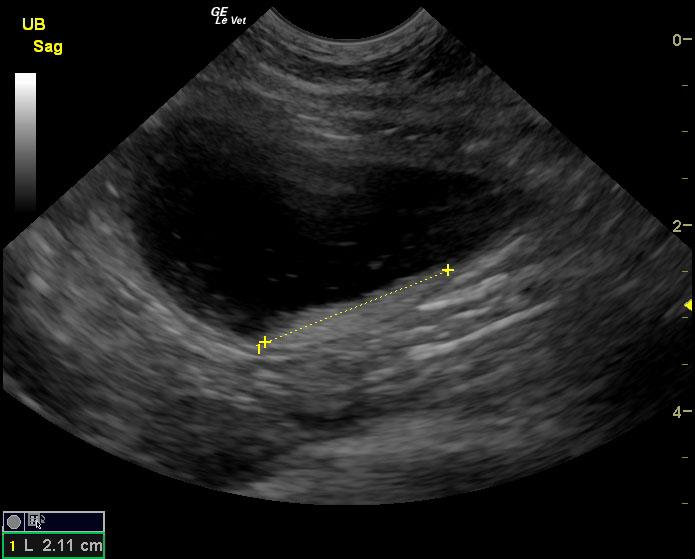

The urinary bladder in this patient revealed dependent debris that measured 2.1 cm in length. The bladder wall presented minor, apical ventral wall thickening. Suspended debris was also evident. The bladder wall thickening appeared to be concentric throughout with some loss of mural detail, and measured 0.4 cm at minor repletion. The pelvic urethra was also thickened. These images are most consistent with interstitial cystitis with minor potential for bladder lymphoma. The kidneys revealed largely normal size and structure; corticomedullary definition and ratio (cortex 1/3 of medulla) were essentially maintained with minor loss of curvilinear pattern. The cortices presented largely uniform texture with some echogenic changes that are not likely of clinical significance at this time.